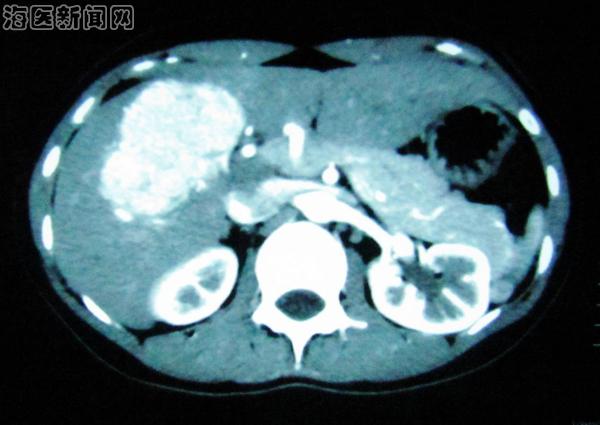

据肝胆外科主任贾长库博士介绍,肝中叶包括左内叶和右前叶,其脏面为动脉、门静脉、胆管、淋巴管及神经汇成的第一肝门,并临近诸管道分叉部;膈面为肝静脉汇入下腔静脉处的第二肝门;肝背侧借助于数目不等的肝短静脉与肝后下腔静脉段相邻,即第三肝门。该患者肿瘤位于肝中叶的Ⅴ、Ⅷ段,若行右半肝切除,手术相对简单,但切除的肝脏组织过多,术后发生肝功能衰竭的可能性加大;若行肿瘤的局部切除,切除范围又太小,万一是恶性肿瘤,则不符合切除原则,理想的切除范围是行Ⅴ、Ⅷ段切除,既保证了足够的肿瘤切除范围,又最大限度的保留了正常肝脏组织,但手术难度也随之加大。

术前CT